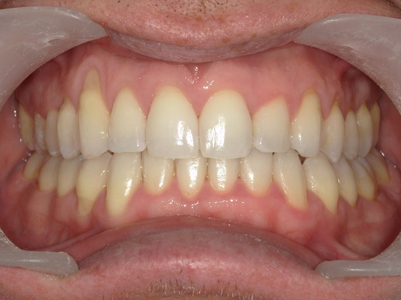

Présentation cas n°1 :

Présentation cas n°2 :